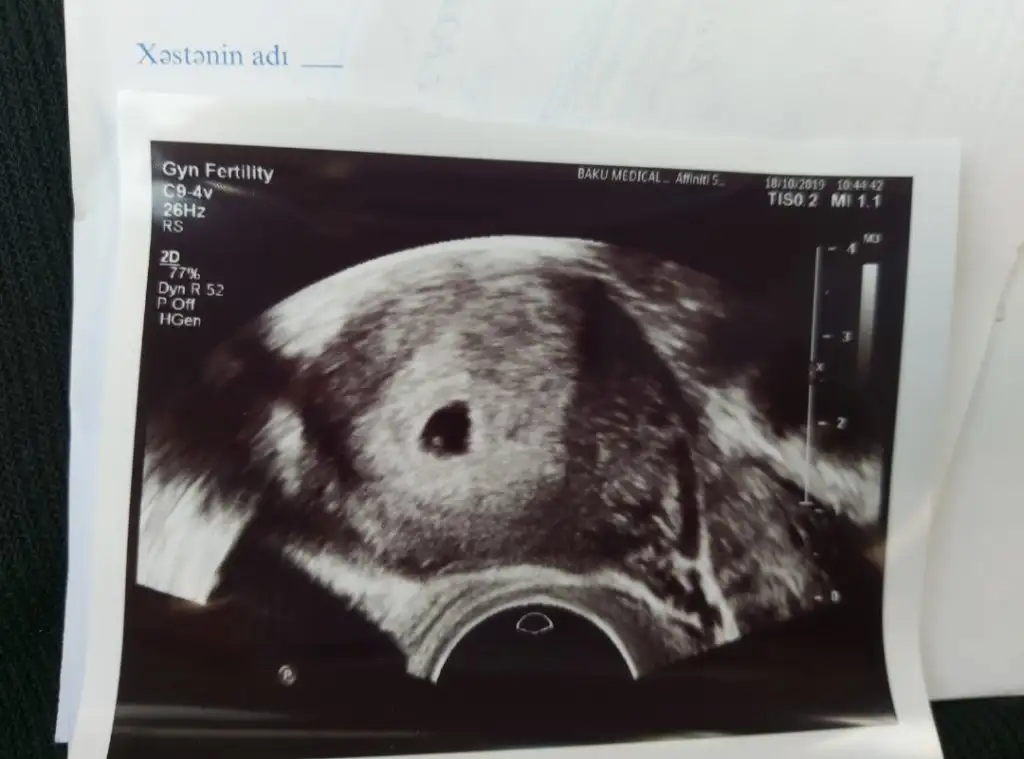

Gözünüz aydın darısı başımıza artıkkizlaaarr, bizim sayın bebedoktor 5haftalik dedi, hatta minik kalp atişlari bile varmiş cok şukur. ama doktor makina algilamaz, haftaya cuma gel, net duyariz dedi

evet ben varim mesela. 7ekimde 3,31di degerim. bu konu da bana ait, en basinda uzun yazmistim, okuya bilirsin. 11gun once 3.31le hic umudum yoktu, ama bugun keseyi bile gorduk. 7ekim 3,31olan degerim 14ekimde 590di. umut hep varÇok teşekkür ederim biraz da olsa umutlanıyorum acaba benim durumumda olup sonradan artan olmuş mudur

Bebegini keseyi kalp atisini duydunmu bu peki bu degerle